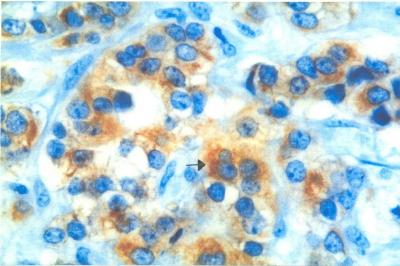

Figure 1. Histological section of IDC showed immunopositivity for Bcl-2 in the cytoplasm (magnification x400)